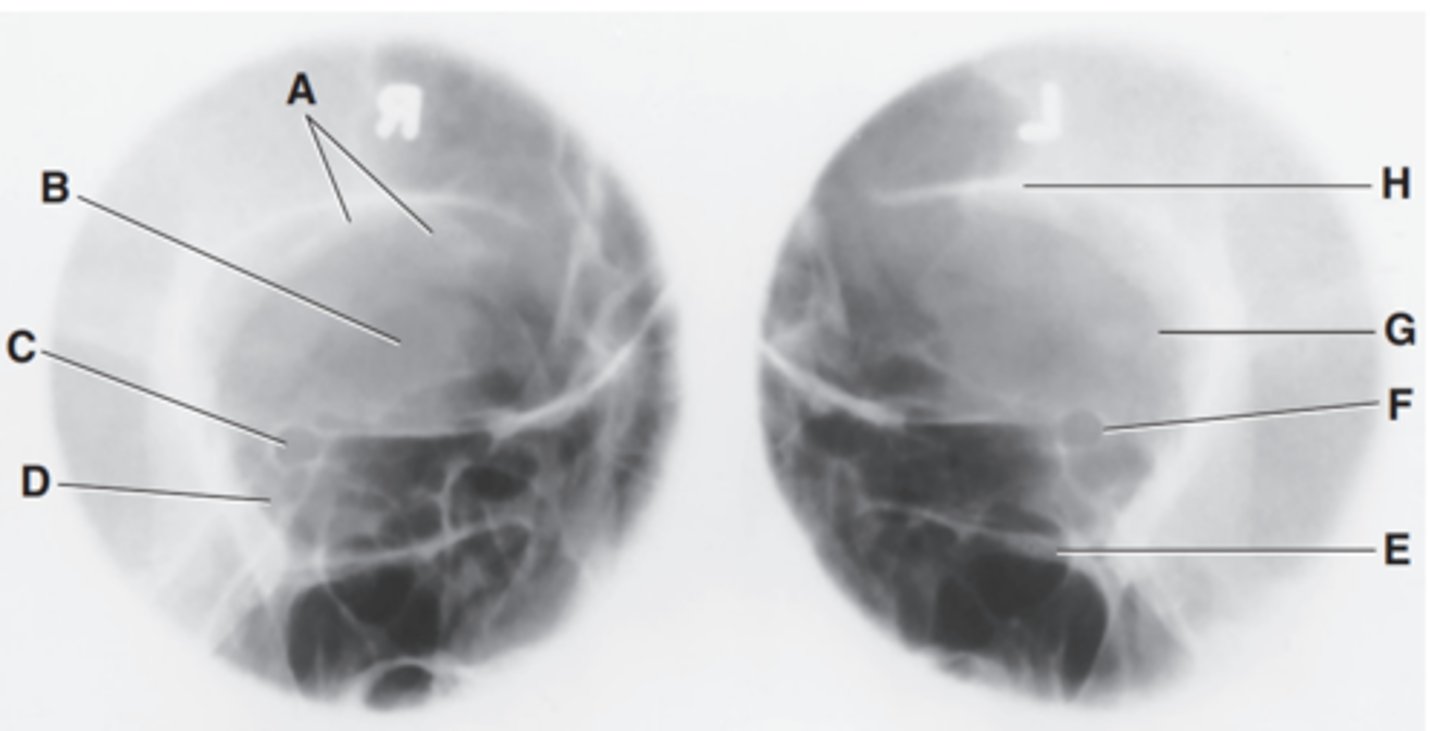

EAM

Label A

Mastoid portion of temporal bone

Label B

Occipital bone

Label C

Lambdoidal suture

Label D

Clivus

Label E

Dorsum sellae

Label F

Posterior clinoid processes

Label G

Anterior clinoid processes

Label H

Vertex of cranium

Label I

Coronal suture

Label J

Frontal bone

Label K

Orbital plates

label L

Cribriform plate

Label M

Sella turcica

Label N

Body of sphenoid (sphenoid sinus)

Label O

Petrous portion of temporal bone

Label P